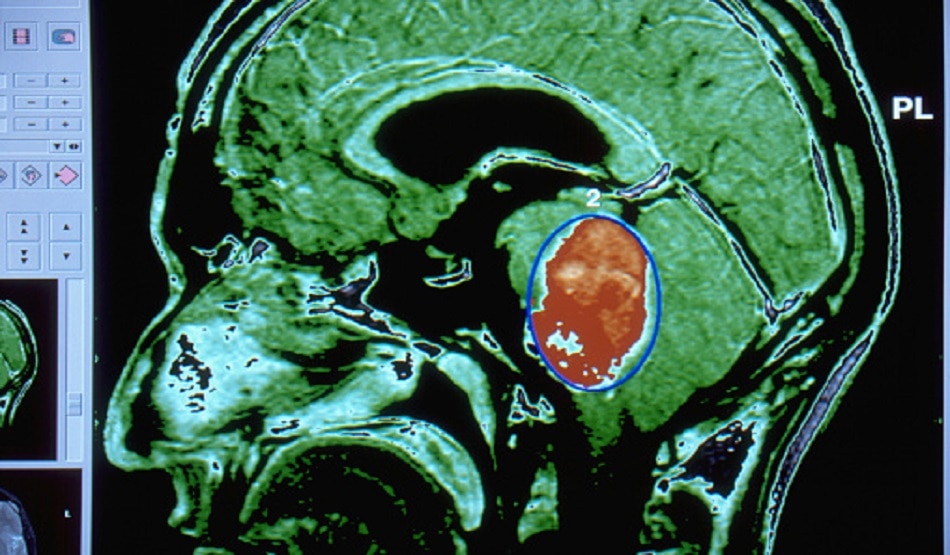

ब्रेन ट्यूमर ऑपरेशन के दौरान युवक की निकाली गई हड्डी गायब, थाने पहुंचे परिजन

मध्य प्रदेश के इंदौर में एक शख्स ने निजी अस्पताल पर सनसनीखेज आरोप लगाए हैं. युवक के मुताबिक ब्रेन ट्यूमर के ऑपरेशन के दौरान अस्पताल प्रबंधन ने उसके सिर की हड्डी निकाल कर रख ली.

मामला उज्जैन के ज्योतिनगर का है.  सुरेश परमार के 33 साल के बेटे के ब्रेन ट्यूमर का ऑपरेशन इंदौर के सीएचएल अस्पताल में 20 जून को हुआ था. परिजनों ने बताया कि उन्होंने इसके लिए दूसरे शहर से डॉक्टर को बुलवाया था. (सांकेतिक तस्वीर/Getty)

युवक के मुताबिक न्यूरो सर्जन ने उसके आधे सिर की हड्डी निकाली और अस्पताल में ही रखवा दिया. कहा गया था कि चार माह बाद ब्रेन के रिकवर होने और ट्यूमर ठीक होने के बाद उस हड्डी को दोबारा लगा दिया जाएगा. परिजनों के मुताबिक ऑपरेशन के बाद रिकवरी होने पर जब वो हड्डी लगवाने के लिए अस्पताल पहुंचे तो अस्पताल की तरफ से उसे दूसरी हड्डी लाने को कह दिया गया.

विशेषज्ञों के मुताबिक ऐसी हड्डी पांच साल तक खराब नहीं होती है. उसे अस्पताल में सुरक्षित रखा जा सकता है जिसे फिर से उसी मरीज को लगाई जा सकती है जिसके शरीर से पहले उसे बाहर निकाला गया है. बता दें सिर की हड्डी को दिमाग का सेफ्टी वॉल कहा जाता है जो ब्रेन को सुरक्षित रखती है. (सांकेतिक तस्वीर/Getty)